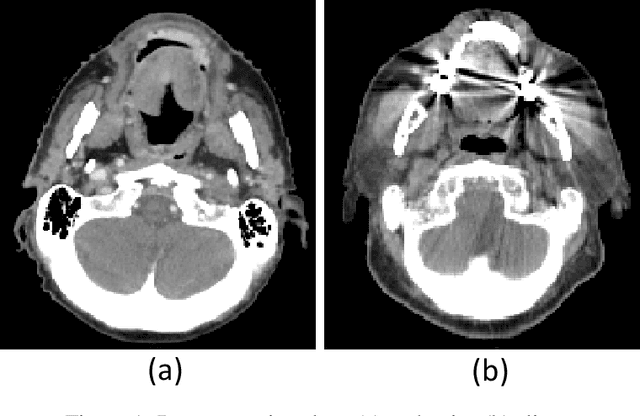

Abstract:The Wasserstein distance is a powerful metric based on the theory of optimal transport. It gives a natural measure of the distance between two distributions with a wide range of applications. In contrast to a number of the common divergences on distributions such as Kullback-Leibler or Jensen-Shannon, it is (weakly) continuous, and thus ideal for analyzing corrupted data. To date, however, no kernel methods for dealing with nonlinear data have been proposed via the Wasserstein distance. In this work, we develop a novel method to compute the L2-Wasserstein distance in a kernel space implemented using the kernel trick. The latter is a general method in machine learning employed to handle data in a nonlinear manner. We evaluate the proposed approach in identifying computerized tomography (CT) slices with dental artifacts in head and neck cancer, performing unsupervised hierarchical clustering on the resulting Wasserstein distance matrix that is computed on imaging texture features extracted from each CT slice. Our experiments show that the kernel approach outperforms classical non-kernel approaches in identifying CT slices with artifacts.